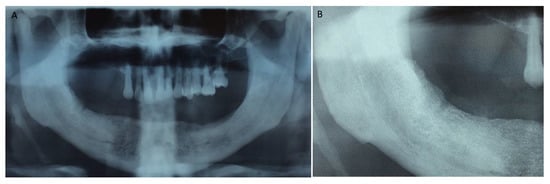

Figure 1, Figure 2, Figure 3, Figure 4, Figure 5, Figure 6 and Figure 7 show the progress of treatment in one of the patients of the test group. In Figure 3 reduction of the medullar space is visible, that may create a chronic ischemic area susceptible to necrosis.

Figure 2.

Pre-operative orthopantomography of the same MRONJ patient showing bilateral defect; (A) shows the panoramic view; (B) shows more detail of the right side of the mandible.

Figure 3.

Pre-operative CBCT of the MRONJ patient, showing a reduction in the medullar space.